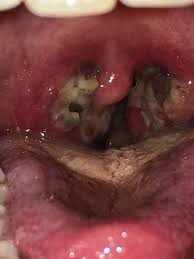

I Should Probably Get My Tonsils Removed Right I M 21 M And I Was Covid And Strep Throat Tested This Past Thursday 8 20 Covid Test Was Negative Strep Was Positive Been On

I Should Probably Get My Tonsils Removed Right I M 21 M And I Was Covid And Strep Throat Tested This Past Thursday 8 20 Covid Test Was Negative Strep Was Positive Been On from preview.redd.it